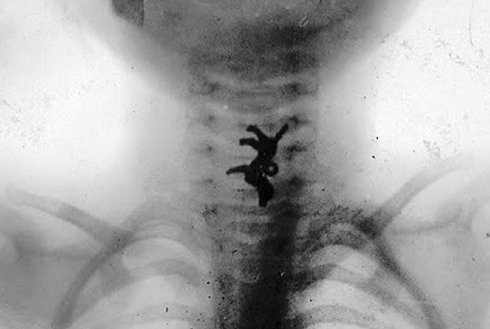

Mutter Museum, el museo del terror

Mutter Museum es un museo de patologías médicas, equipos médicos antiguos y

exposiciones biológicas, ubicado en el Colegio de Médicos de Filadelfia.

Este curioso museo es conocido por su gran colección de cráneos, cuerpos

con malformaciones, esqueletos bien conservados. (Todo de cuerpos reales)